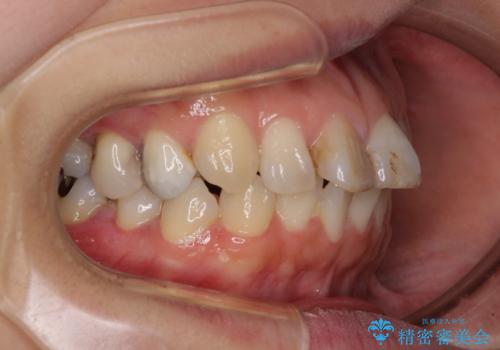

- 前歯のデコボコを治したいとのことで来院された患者様です。

上下顎ともに歯列全体の後方移動とIPR(歯と歯の間を削る)によってデコボコが解消するように設計し、インビザラインにより治療を行うこととしました。

しっかりと装着時間を守ってくださったのですが、途中妊娠にともなう悪阻や出産といったイベントがあり、予定よりも治療期間が長くなりました。